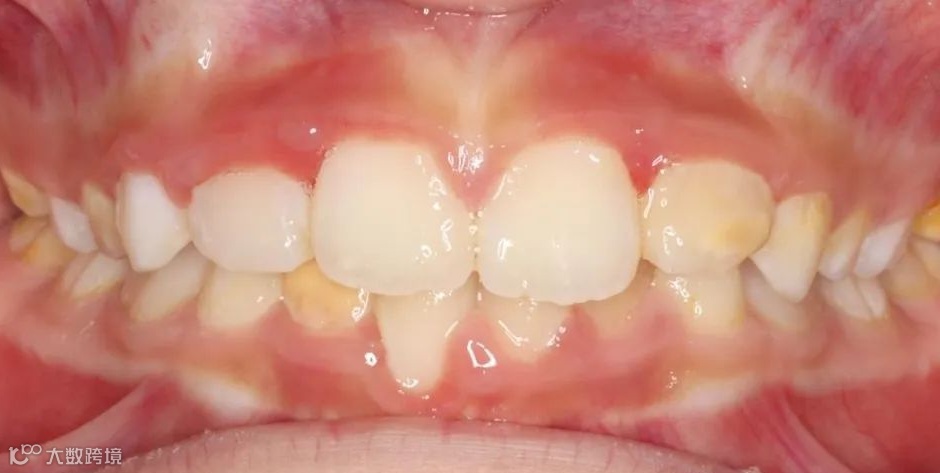

治疗前正面咬𬌗相

治疗后正面咬𬌗相

治疗前正面微笑相

治疗后正面微笑相